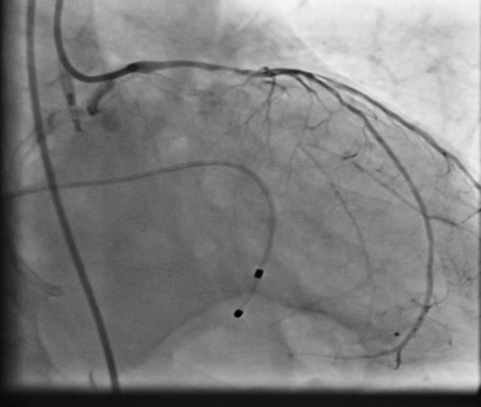

PCIof right coronary artery was initiated on IABP support with amplatz left1 guided catheter and vessel was crossed with great difficulty in repeatedattempts by fielder XT followed by GAIA 2 wire over corsair microcatheter. Microcathetercould not be crossed beyond mid segment calcified CTO, so balloon dilation with0.75 mm balloon was done after which again microcatheter could not be trackedbeyond mid part. Butwe were able to exchange wire to allstar followed by rotawire byplacing microcatheter in mid segment after balloon dilation by 0.75 mm balloon. Rotablation wasdone with 1.25 mm burr at 1,60,00 rpm repeatedly from proximal to mid distalpart. Lesionstill looked unprepared as repeated postdilation with2.25*15 mm followed by 2.5*15 mm non compliant balloon at high pressures showedunexpanded balloon. Againlesion preparation was done with 2.5*15 mm wolverine cutting balloon repeatedlyat high pressures which led to adequate luminal gain and calcium cracks as seenon IVUS run. AfterIVUS run again high pressure balloon dilation was done with wolverine 2.5*15 mmballoon followed by 2.5*12 mm non compliant balloon at 28 atm toadequately prepare the lesion before stent deployment. Stentingwas done with 2.5*32 mm DES, 2.75*32 mm DES, and 3*24 mm DES from distal toproximal in overlapping fashion. Thenfinally high pressure post dilation was done with 2.75*15 mm followed by 3*15mm non compliant balloon and adequate stent expansion was achieved with TIMI 3 flow.

Rightcoronary artery was well revascularized with adequate stent expansion and nosignificant complications. Patientwas weaned off from IABP support next day and regained his rhythm after 2 daysand then temporary pacemaker support was removed. Hewas planned for a staged rotablationguided PCI to left coronary system as he developed mild renal dysfunction whichgradually improved in hospital before discharge.